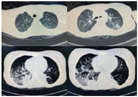

辅助检查:(1)脑脊液检查:生化指标、蛋白均在正常范围内。血清甲状腺功能、肌酶均阴性。(2)痰培养:铜绿假单胞杆菌。G实验、GM实验均阴性。(3)胸部CT:双肺炎症,双肺背侧肺野部分不张并实变(图1)。(4)膈肌功能超声:呼吸末膈肌厚度约1.1 mm,吸气末膈肌厚度约1.4 mm,膈肌增厚度约27%,膈肌移动度10 mm(图2)。(5)支气管镜:右肺中下叶、左肺下叶各级支气管可见大量痰液(图3)。

经后续20 d康复治疗:患者言语清晰,胸部CT双肺炎症明显吸收(图6),膈肌功能较前改善(图7)。拔出气切管。目前患者上、下肢关键肌肌力均达Ⅴ级。坐位平衡3级,可独立步行。ADL BI评分85分(进食10分、修饰5分、穿衣10分、控制大便10分、控制小便10分、如厕10分、床椅转移15分、平地行走15分)。